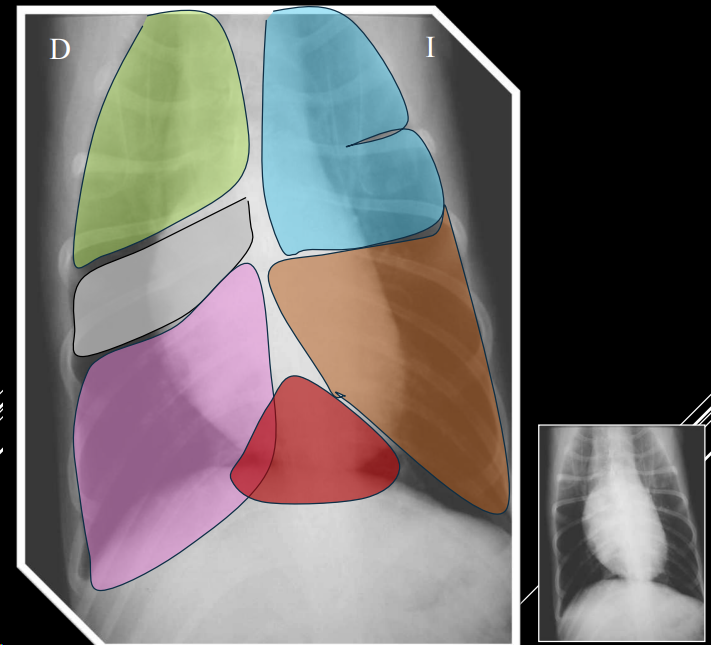

PULMONES

- Proyecciones LL y VD.

- izquierdo 2 lobulos, derecho 4 de normal no se ve mucho. solo se ven los bronquios en patologías

PATRÓN NORMAL

- Opacidad baja (aire en bronquios, bronquiolos, alveolos).

- Vasos visibles como líneas ramificadas.